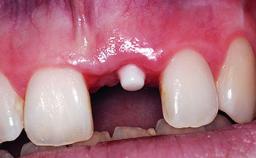

Replacement of an Ankylosed Upper Left Central Incisor: Bone Augmentation and Socket Grafting, Late Placement of an RC Bone Level Implant

Bone Augmentation Horizontal|Simultaneous|Staged

Augmentation Materials Autogenous chips|Xenogenous

Bone Volume Deficient horizontally, requiring prior grafting